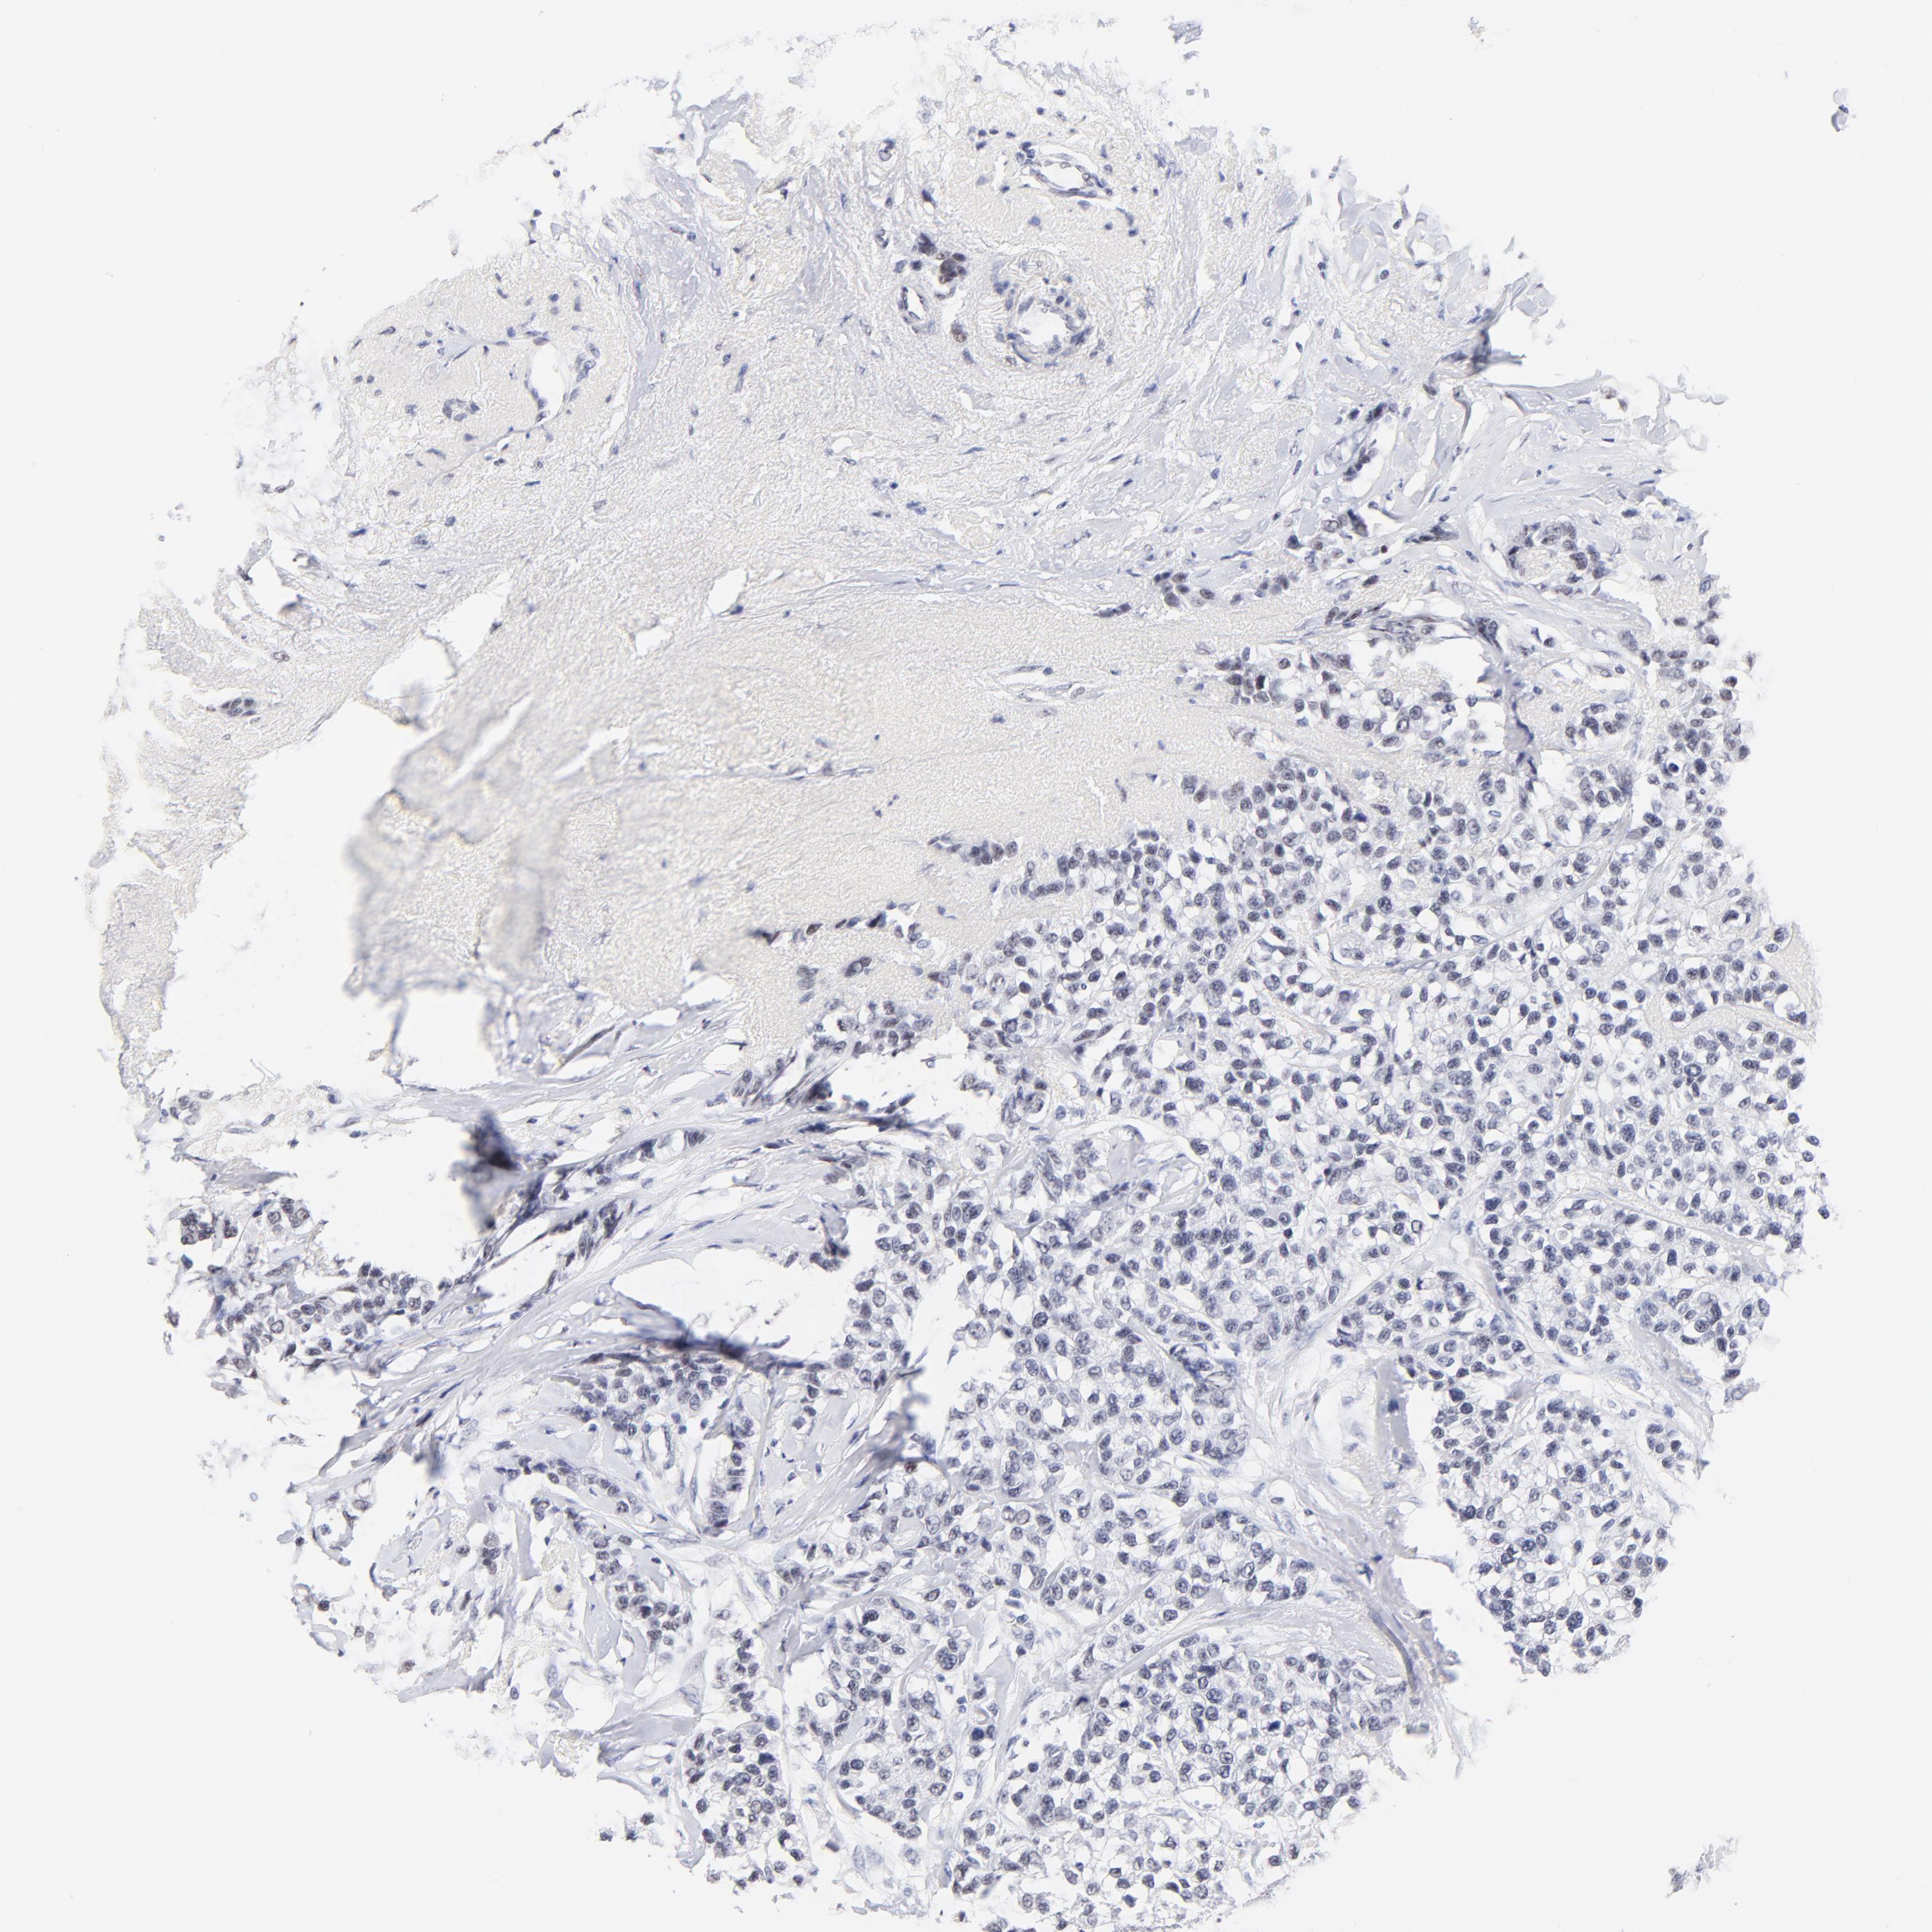

BRCA TCGA BRCA VALIDATION PROTEIN EXPRESSION

ANTIBODIES

AND

VALIDATION